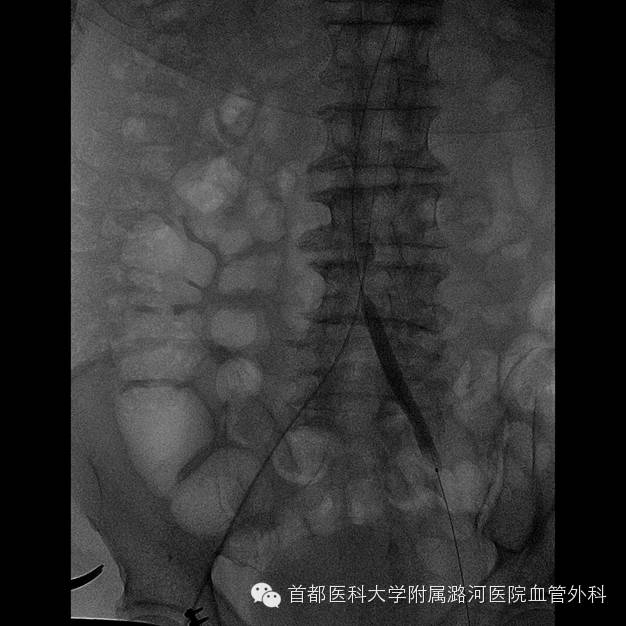

导丝通过右侧髂总动脉起始段受阻,其余导丝无阻力通过。

于右侧髂动脉内低压造影显示右侧髂总末端至髂外动脉全程充盈缺损。

证实右侧髂总动脉起始端重度狭窄基础上继发血栓形成;以血栓为主。